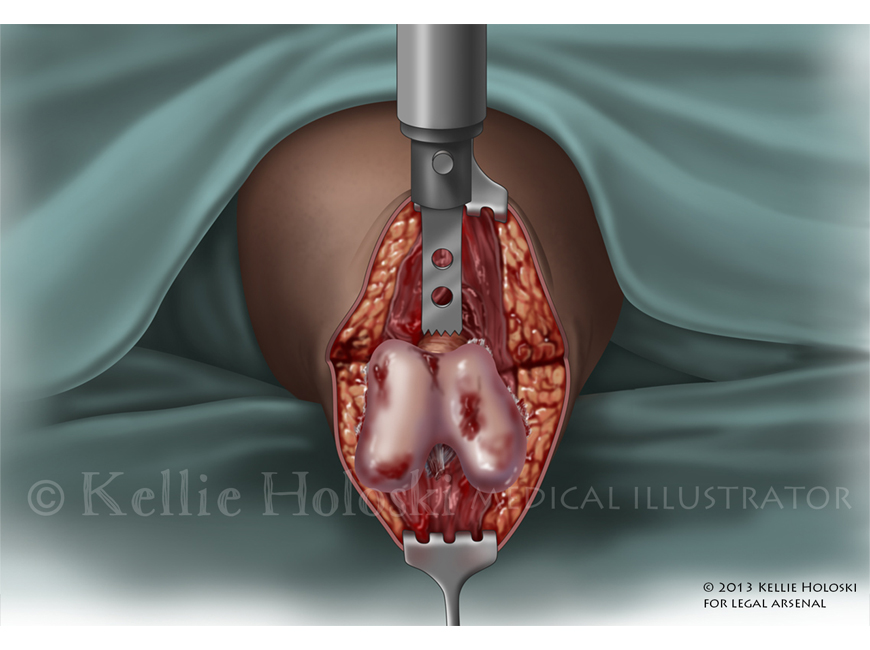

Use of Bone Saw for Amputation,

Adobe Photoshop

Courtroom exhibit;

©Kellie Holoski -